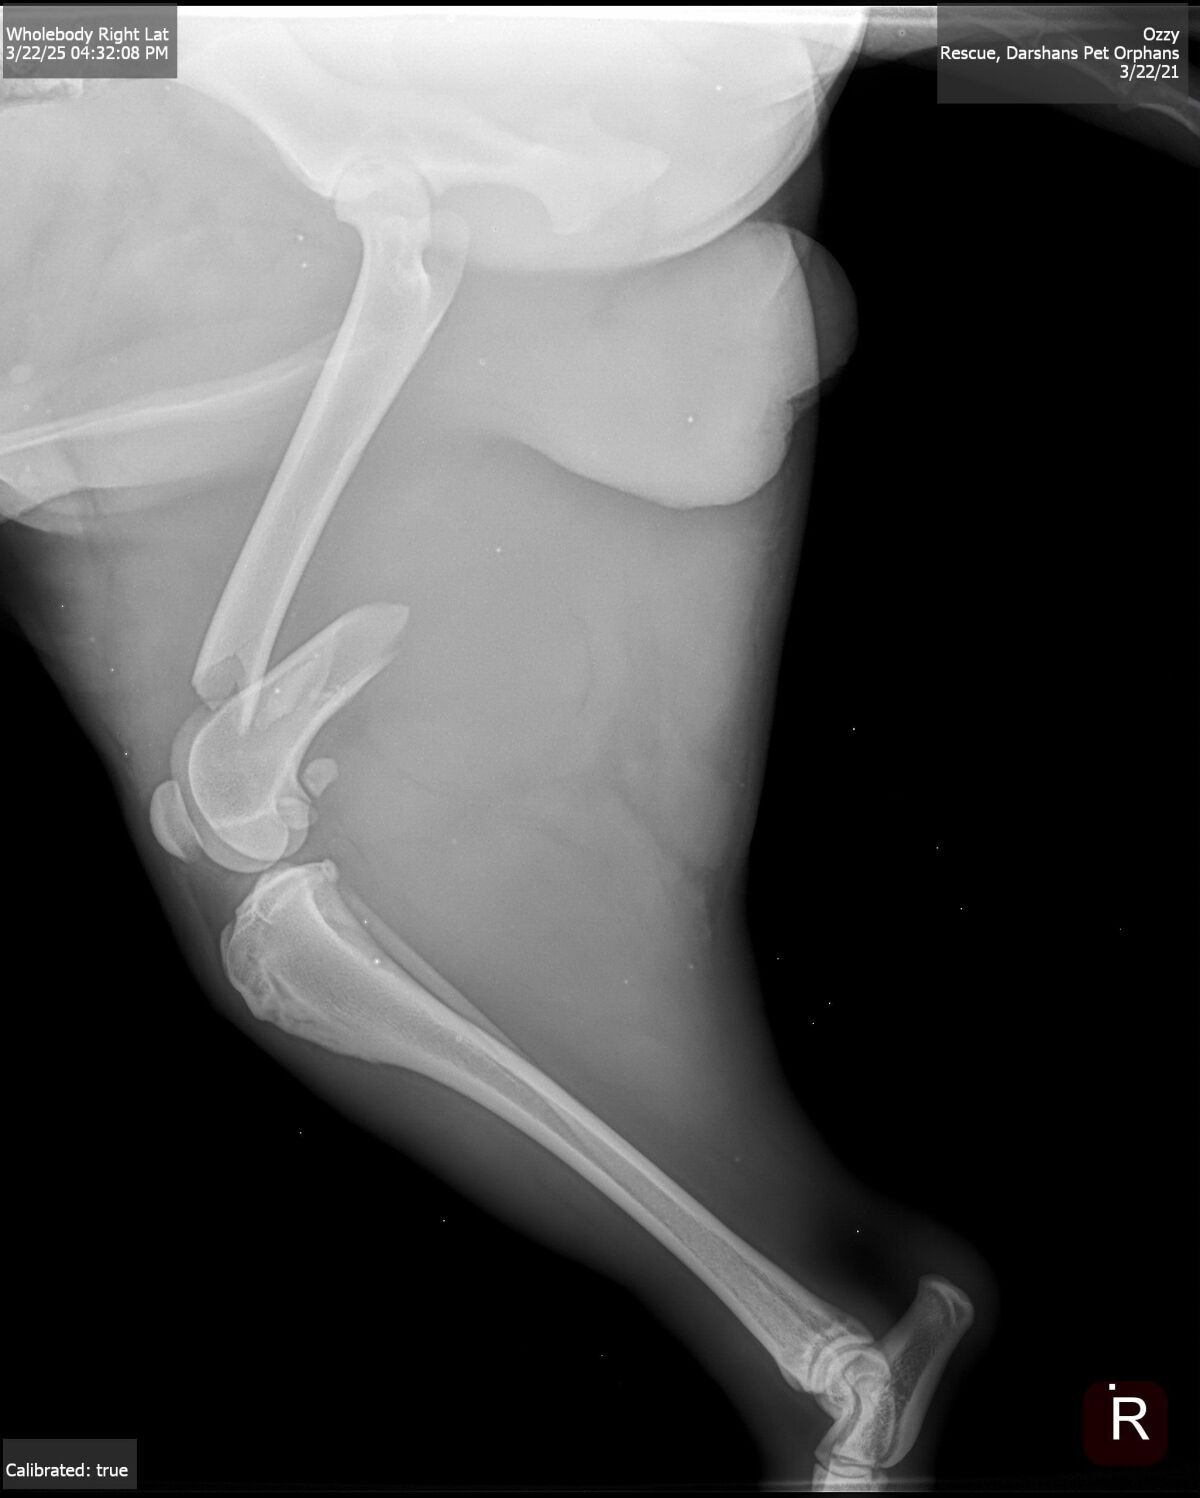

He had suffered for days with multiple fractures. He has two badly broken legs. His surgeries will be costly and not without risk of infection due to hardware placement. But Oreo has shown us he WANTS TO LIVE. He wags his tail in his kennel, despite his severe pain he must be in.